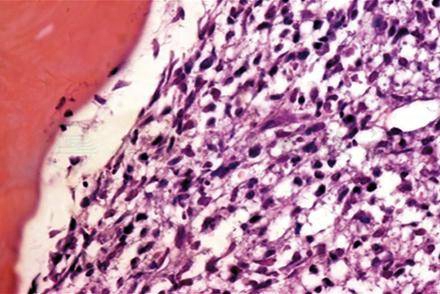

有时需用PCR技术来帮助诊断,特别困难的病例需骨髓穿刺,其标本再进行组织病理学(图4)和免疫组织化学检查(图5),明确诊断。

图4 骨髓穿刺组织标本组织病理检查见骨髓中瘤细胞异型性大,胞核染色深,部分细胞质呈空泡状 HE×300